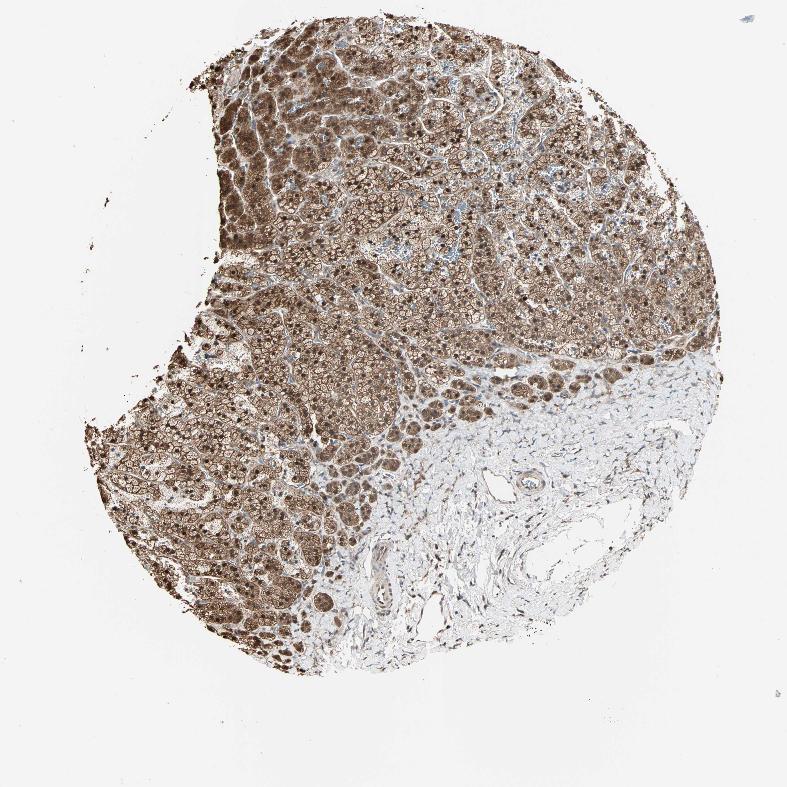

ADRENAL GLAND - Antibody stainingi

Antibody staining in the annotated cell types in the current human tissue is reported as not detected, low, medium, or high, based on conventional immunohistochemistry profiling in selected tissues. This score is based on the combination of the staining intensity and fraction of stained cells.

Each image is clickable and will lead to virtual microscopy that enables deeper exploration of all samples and also displays staining intensity scores, fraction scores and subcellular localization as well as patient and tissue information for each sample.

Antibody HPA007716

Glandular cells High